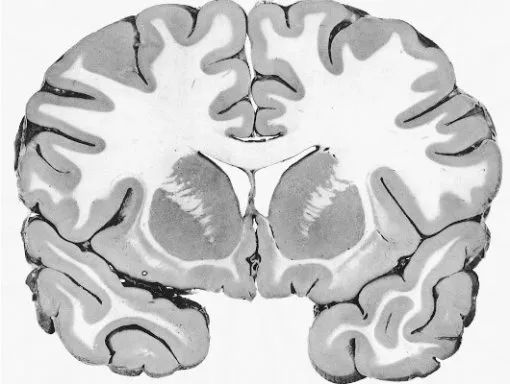

当我们把外面这些东西都剥去后,剩下的就是这个:

这个看起来很荒唐的东西是宇宙里我们已知的最复杂的东西,重约三磅,功率约等于20瓦,相比之下,一个同等强大的计算机的功率约是2千4百万瓦。Tim Hanson教授把大脑称为“已知的信息密度最大、最有结构性,并且最能够自我构建的物质”

我们先通过一个脑半球切片来看一下大脑的几个主要部分:

我们把大脑从头部取出,然后移除左半球,然后我们就能好好看看内部了。

接下来,我们退出去,再看一下脑的横切面,这次不是从前往后切,而是从中间切。

大脑的材料可以分为灰质和白质。灰质看上去颜色更深,由神经元的细胞组成,白质则主要由链接轴突组成。白质之所以是白色是因为这些轴突通常被髓鞘包裹着。

灰质主要有两个部分——边缘系统的内部和脑干,以及皮质外层硬币那么厚的部分。剩下来的大块的白质主要就是皮质神经元的轴突组成的了。皮质就像一个指挥中心,把很多命令通过白质中的轴突传播下去。